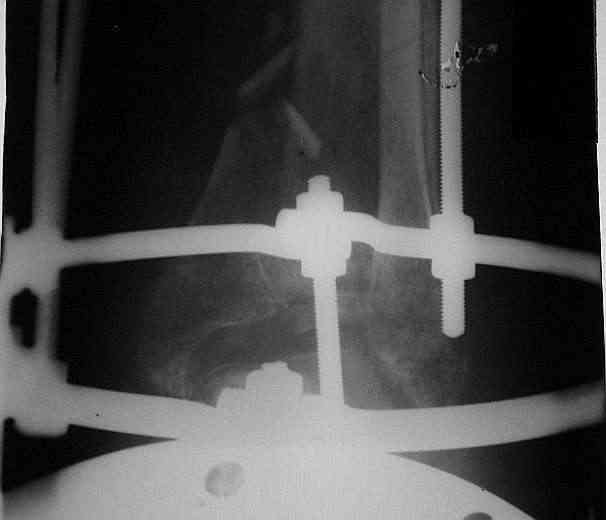

Было решено, уже по ходу операции, выполнить артродез болтом-стяжкой, тем самым компрессируя резецированные суставные поверхности и смещая стопу латерально, дабы нивелировать варусную деформацию и восстанавливая тем самым опорную ось всей конечности.

Вчера (прошло около 8 месяцев)больной обратился ко мне в очередной раз с жалобами на боли умеренно-жгучего характера в области выстояния концов болта-стяжки. На момент осмотра:укорочение левой нижней конечности на 1,5 см; гипотрофия медиальной группы мышц голени и четырехглавой мышцы бедра; передвигается без дополнительной опоры в ортопедической обуви на растояние до 5 км; работает приемщиком цветных металлов (приходится перетаскивать грузы). Нарентгенограмме, насколько это можно видеть, костного блока сформировать не удалось, но движений в голеностопном суставе нет - ни активных, ни пассивных. Послеоперационные рубцы б/о; свищей и нагноения не было. Активно больногонаблюдать не приходилось, т.к. проживает в другом городе.

ЗЫ: Прошу прощения за очень низкое качество представленных ренгенограмм. Буду очень признателен за комментарии.